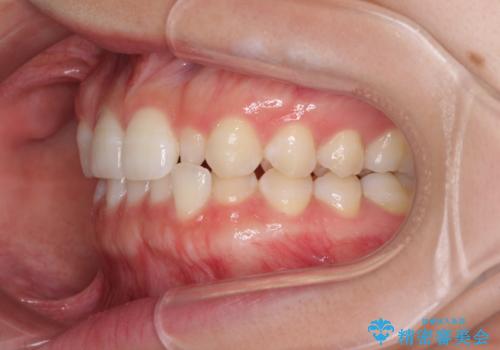

- 1年後に海外に転居するため、気になる前歯を矯正治療で整えたいとのことで来院された患者様です。

下顎は叢生が強かったため、奥歯までワイヤーを装着し、上顎は前歯の一部のみ気になっていたので、その部分にだけワイヤー装置を装着することとしました。

部分矯正は、適応となる症例が限定されます。

こちらの患者様は部分矯正が可能な、非常に珍しい方でしたが、部分矯正を希望される患者様の大半は、全顎矯正が必要となります。